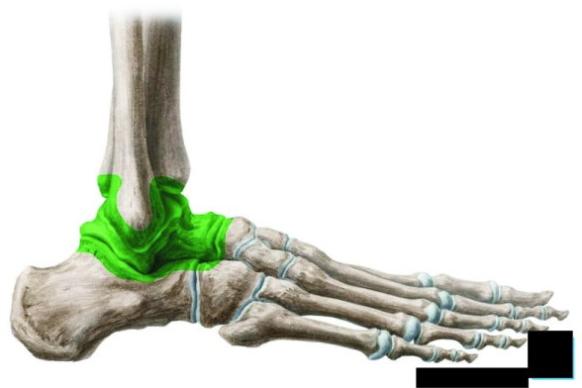

OSTEOARTRITIS SKOČNOG ZGLOBA

Zglobovi stopala su zglobovi između kostiju potkoljenice, tibije i fibule, i kostiju gležnja, te zglobovi između pojedinih kostiju stopala ( slika 2 )

Zglobove možemo podijeliti na sljedeći način:

&skočni zglob koji se sastoji od

&gornjeg skočnog zgloba ( articulatio talocruralis, slika 3. i 4. )

&donjeg nožnog zgloba ( articulatio talocalcaneonaviculare, slika 5. i 6.)